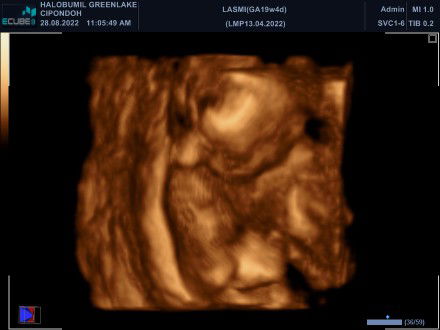

[Sudah Berakhir] Si Bumil harus pilih jalan mana ya?